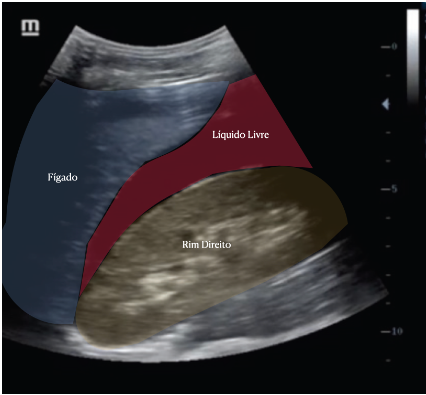

Liquido livre

Aspecto no USG?

A

Imagem anecoica que contorna orgãos, dando aspecto de semilua